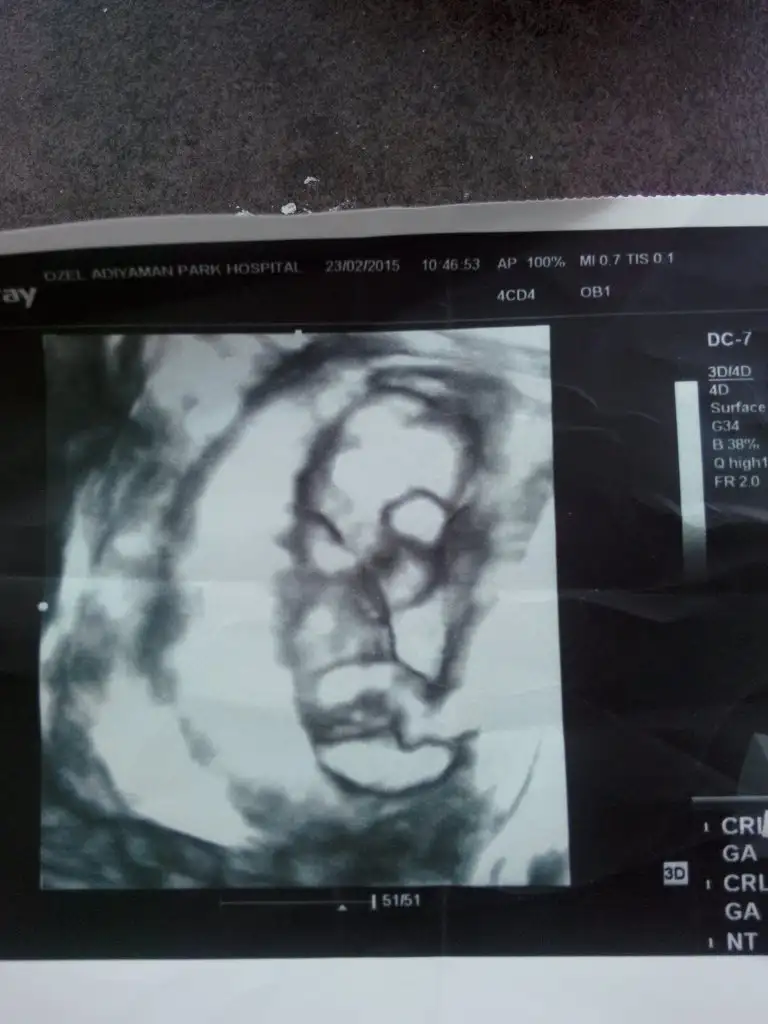

dr soylemeden siz gorun genital nub teorisi ( bebegin cinsiyeti)

Hayırlı olsun benim tahminimede erkekti bence dk erkek demis iste degismez artik rahat ol

Ultrason a girmeden cikolata ye hateketlenir karnin tok olsun ama görecekesin erkek diycek yine ama iciniz rahat etsin hayırlı olsun